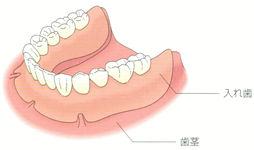

奥歯を含めて複数の歯を失った場合

部分入れ歯の場合

・金属のバネをかける健康な歯に負担がかかる。

・常に違和感がある ・金属のバネが見えて、見栄えが良くない

・金属バネの間に食べ物が詰まりやすく、丁寧に掃除をしないと、虫歯や口臭の原因となる

インプラントの場合

・インプラントは時間の経過とともにあごの骨と結合するため、歯を支える力は健康な歯とほとんど変わらない

・単独で処置するので、健康な歯をそのまま保てる

・外観も機能も天然の歯と変わらない感覚が得られ、違和感がない

・特別なケアの必要がない